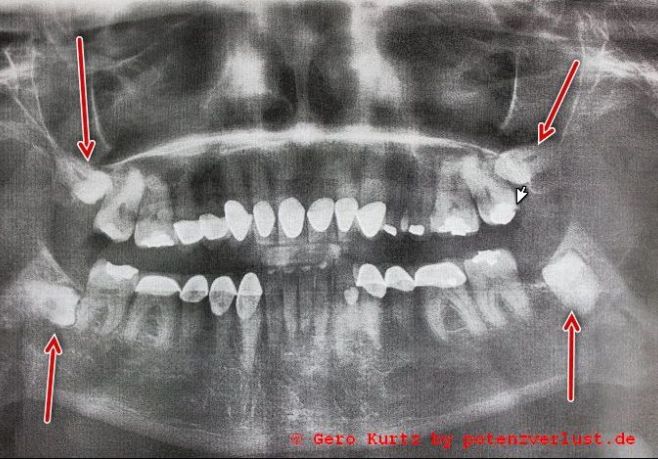

Dort wurde noch einmal das Gebiss mit einem modernen Ganzkieferröntgengerät gescannt. Der Arzt hat sich das dann angeschaut und gemeint, dass die Extraktion unten recht gefährlich sei, da die Zähne sich schon unter den anderen geschoben haben. Ihm ist lieber, wenn dies unter Vollnarkose ausgeführt wird, damit ich mich bei der OP nicht bewege. Eine Lähmung des Gesichtsnervs könnte davon die Folge sein, falls dieser dadurch beschädigt wird. In diesem Falle würde die Vollnarkose auch nichts kosten, da sie medizinisch notwendig sei. Praktischerweise befindet sich eine Anästhesistin im Hause, die in solchen Fällen dann mit dem Team herüberkommt. Die Zahnklinik bildet einen größeren Komplex mit vielen anderen Arztpraxen. In der DDR nannte man so etwas Poliklinik, jetzt wohl eher Ärztehaus.

Röntgenbild Gebiss

Eines Folgetermins bedurfte es nicht. Zum Schluss habe ich mir noch mein Röntgenbild ausdrucken lassen.

Mit der Überkronung der Zähne habe ich aus Sicherheitsgründen noch ein dreiviertel Jahr lang gewartet. Probleme oder Schmerzen hatte ich in dieser Zeit keine mehr. Auf dem Röntgenbild, welches vor der Überkronung gemacht wurde, war zu erkennen, dass sich die Löcher gut schließen